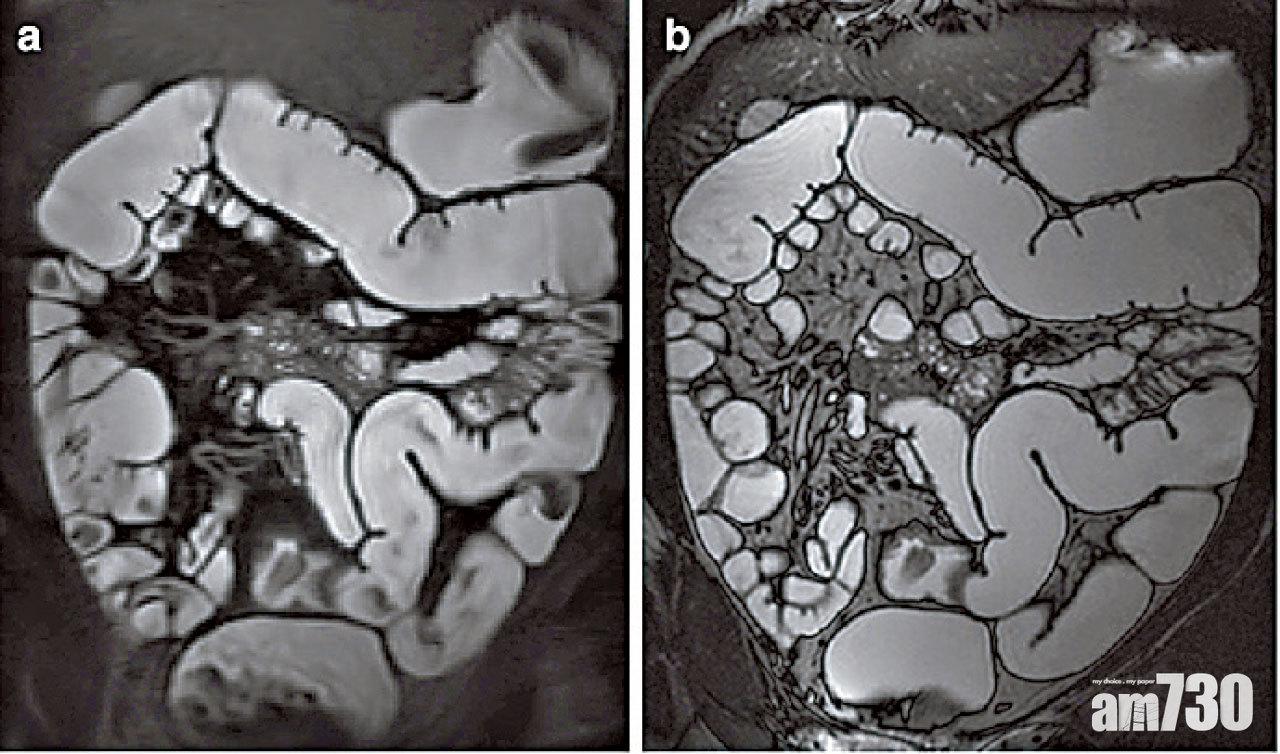

磁力共振掃描腸造影檢查(MRE)同樣可用於評估小腸情況,但與電腦掃描腸造影檢查不同之處是它不涉及電離輻射,因此特別適用於終生需要進行多次檢查的年輕患者。至於磁力共振掃描,則可用於掃描炎症性腸病患者盆骨肌肉層的肛周周圍,以便評估他們有否出現肛瘻及肛門膿腫等問題。

電腦斷層掃描和磁力共振掃描均是非侵入性檢查程序,對評估小腸和消化道以外的併發症尤其有用。醫生使用這些掃描診斷工具,再配合傳統的內窺鏡檢查和血液檢查,可為病人度身訂造合適的治療方案,有助預防他們突然發病及出現併發症。